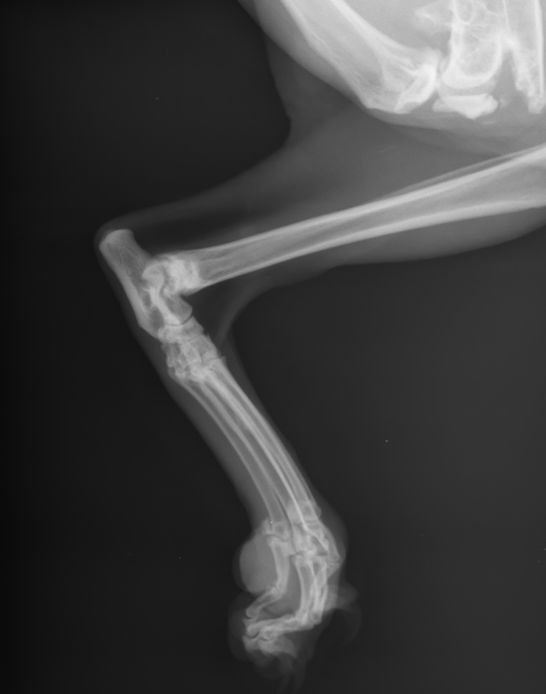

- Травмах и подозрении на переломы — особенно после падения или аварии;

- Болях в спине или хромоте — для выявления грыж, артритов, дисплазий;

- Контроле лечения — например, срастание костей после операции.

- Съемка: делается 1–3 снимка с разных ракурсов.

- Расшифровка: врач-рентгенолог анализирует снимки и готовит заключение.